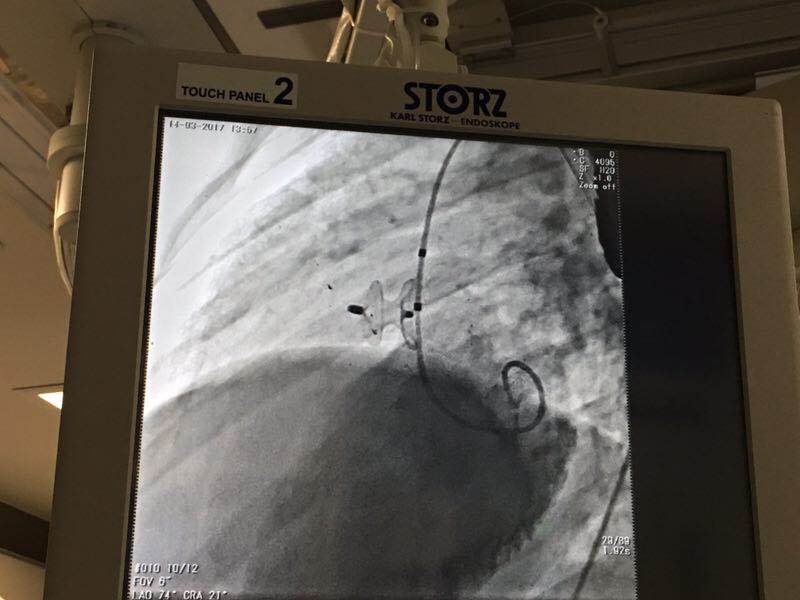

术后造影显示,病人室间隔缺损封堵完全。手术室外一阵欢呼,随之而来的,还有孩子父亲的喜极而泣。听到手术成功的消息,这个高大的男人无法抑制内心的激动,哽咽着向医生和彩神在线网信彩票-彩神通免费版下载-彩神8争霸vlll-彩神购彩购彩大厅-彩神软件陆立根免费版-彩神ll争霸3-彩神ll彩神8-彩神ll争霸彩票-拼搏在线彩神网网页版科技公司的工作人员道谢,感谢他们使自己的孩子迎来了“心”希望。

这例挑战性手术进行的非常成功,用一个10mm 的Cera™膜部VSD封堵器就实现了对病人多孔室间隔缺损的完全封堵。在封堵器准确植入缺损位置的那一刻,现场原本凝重的空气像是融入了冬日雪后的暖阳,温暖了手术室外孩子父母紧握着的冰冷的双手,带来了一阵阵欣喜和感动,也为这位来自北极圈附近的小病人带来了健康人生。这正是对彩神在线网信彩票-彩神通免费版下载-彩神8争霸vlll-彩神购彩购彩大厅-彩神软件陆立根免费版-彩神ll争霸3-彩神ll彩神8-彩神ll争霸彩票-拼搏在线彩神网网页版科技公司使命最好的诠释。